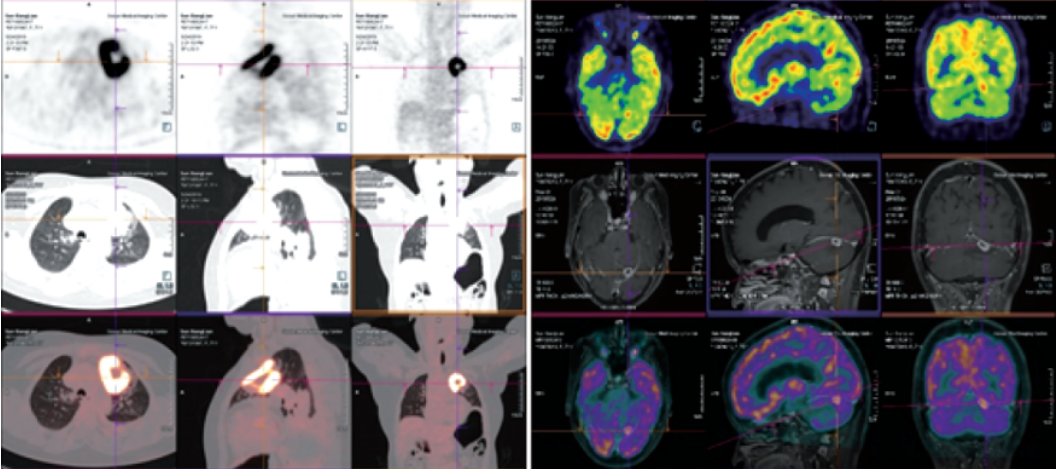

Biograph mCT.S 西門子PET/CT(正電子發(fā)射及計算機(jī)斷層掃描系統(tǒng))

★PET/CT在全身腫瘤的早期篩查、早期診斷、良惡性鑒別、惡性腫瘤的分期、分級、尋找腫瘤原發(fā)病灶、評估療效及監(jiān)測腫瘤復(fù)發(fā)等方面具有重要價值。

本設(shè)備圖像重建矩陣可達(dá)400×400,其分辨率達(dá)到毫米級;提供精細(xì)器官細(xì)節(jié)顯示,對病灶提供精確的可重復(fù)定量分析;顯著提高微小病灶的檢出和確診率。

PET/CT是通過血管內(nèi)注射示蹤劑,采用動態(tài)連續(xù)掃描全身,動態(tài)數(shù)據(jù)分析,跟蹤檢查精準(zhǔn)定位,全身病變無處遁形。

本設(shè)備采用流式掃描技術(shù),可在3-5分鐘完成高質(zhì)量的全身掃描,具有掃描速度快、靈敏度高的特點,可快速檢查全身,提高速度和診斷效率。